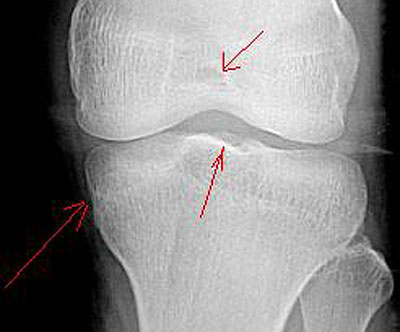

标题: X4122:男 20岁 活动时感觉关节内有东西,活动时疼痛。箭头 [打印本页]

男 20岁  活动时感觉关节内有东西,偶尔疼痛。箭头指的地方有问题吗?

不排除胫骨平台内游离骨片

膝关节正侧位平片未见明显异常。必要时请做ct进一步检查。

关节间隙好窄,mr进一步检查吧!